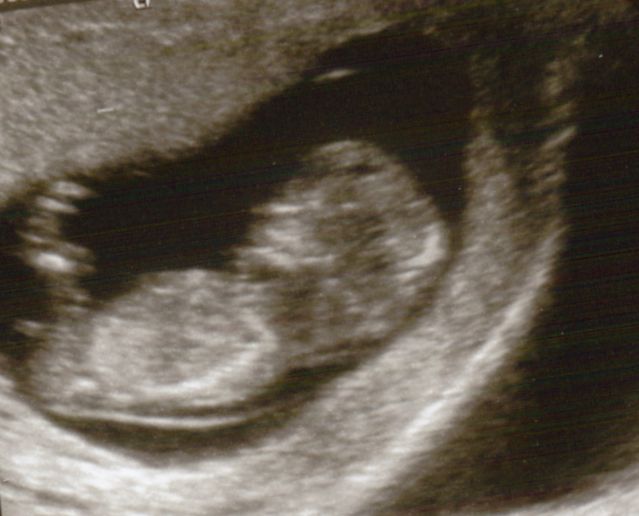

Could you all have a guess at this scan photo girl or boy? I have thought boy for ages as its slightly on the angle but it does look in line with the spine which means girl?!?! Lost

This was 11 weeks :)

Hiya, I had a scan at 11 weeks and it showed girl nub in one shot and boy in another, but after researching even if it showed girl at 11 weeks I wouldnt count on it as the nub generally rises into a boy nub between week 11 and 12 so still time to rise xx

Worked it out properly and I was 12.5 weeks at my scan if that makes things easier?mx

Thinking boy. Slight angle and at 11 weeks there is plenty of time for the nub to rise.